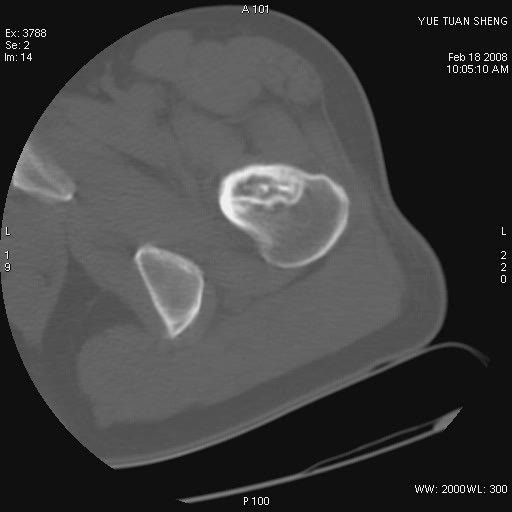

患者,男,56岁,左髋部疼痛1个月,x线:左股骨头高密度影,性质待定,右侧正常。左髋ct如图

左股骨颈区椭圆形磨玻璃样影,边缘明显硬化环环绕,其内见斑点状类钙化高密度影考虑 良性骨病-----骨纤,骨化性纤维瘤,内生软骨瘤。